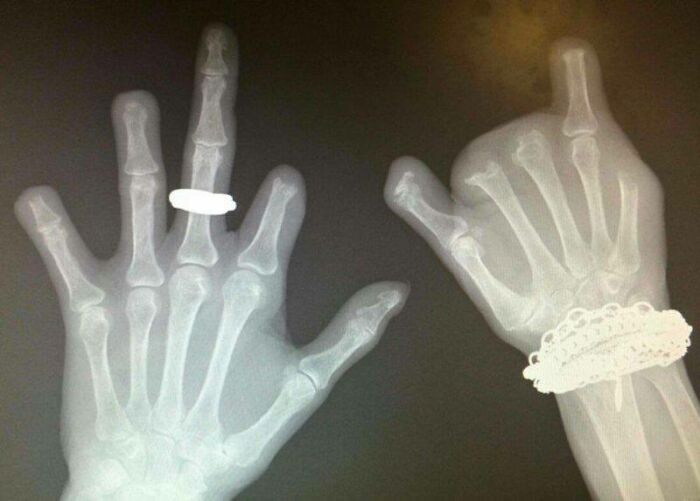

I Just Found My X-Ray From 2010. It Shows An Abnormal Bone Growth On My Right Femur That Has Since Been Surgically Removed